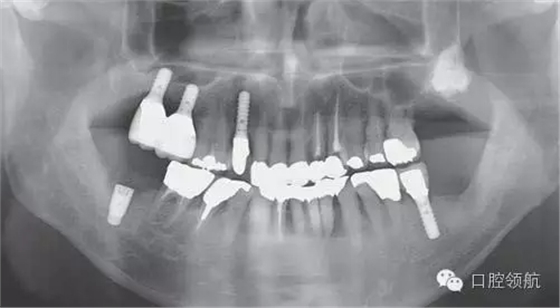

來自外院的(左下第七顆牙)位置種植病例。術(shù)前X線片診斷嵴頂距下頜神經(jīng)管的距離充足。常規(guī)兩次手術(shù)的方法植入1顆種植體。

術(shù)后第2天,右側(cè)頦神經(jīng)區(qū)域感覺異常來本院診療,曲面斷層和CBCT影像顯示,種植體的尖端接觸到了下頜神經(jīng)管(圖1、圖2)。

圖1 植入后的曲面斷層影像。